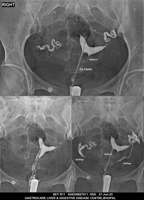

Section: HSG

Total: 49 Cases

All Categories BaM Enteroclysis Loopogram BaE Fistulogram Urethrogram HSG